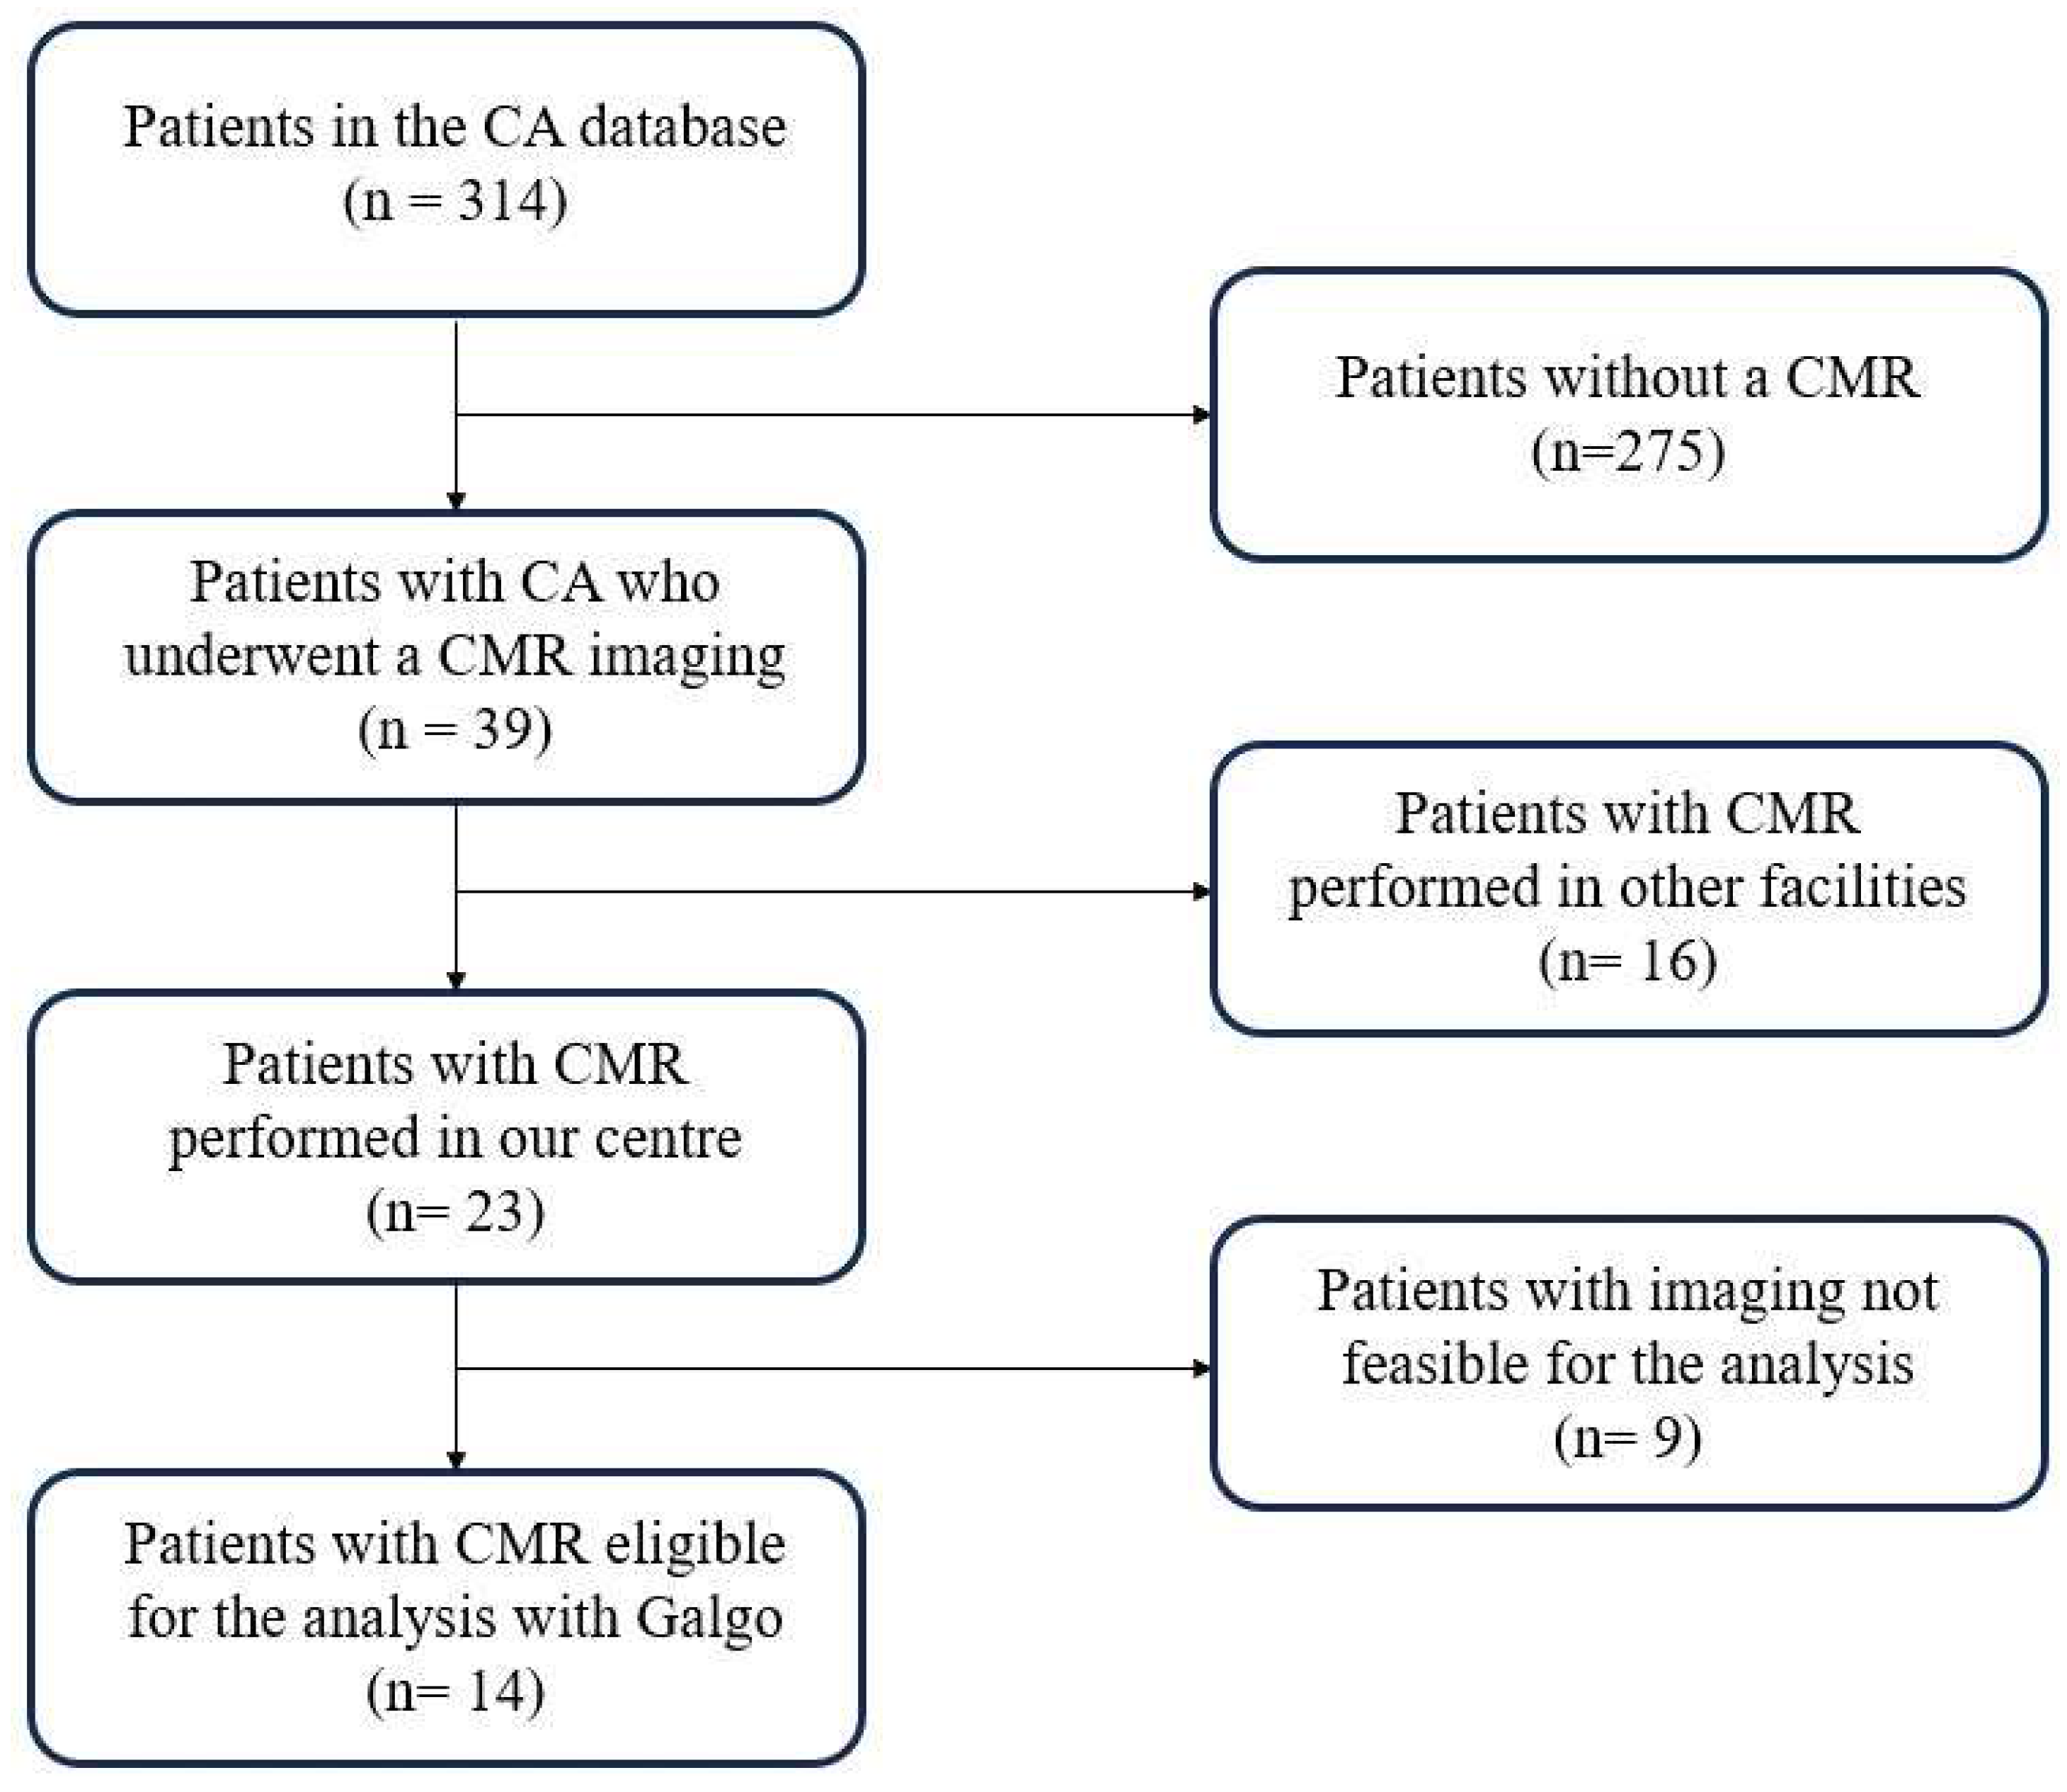

2. Materials and Methods

3.1. Population